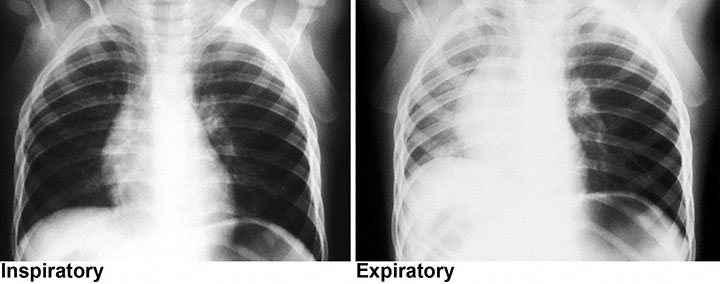

A 4-year-old boy is brought to the emergency department 30 minutes after the sudden onset of shortness of breath and wheezing at a birthday party. Witnesses report that he was acting normally until he was noted to be in distress; they did not see him choke on anything. He has no history of serious illness and receives no medications. His temperature is 37°C (98.6°F), pulse is 100/min, respirations are 24/min, and blood pressure is 90/60 mm Hg. Pulse oximetry on room air shows an oxygen saturation of 95%. Examination shows decreased breath sounds over the left hemithorax. Inspiratory and expiratory chest x-rays are shown. Which of the following is the most likely diagnosis?